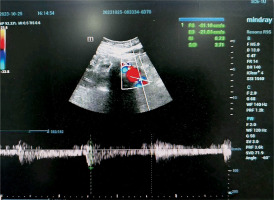

A 66-year-old female farmer was admitted to the hospital after experiencing nausea and vomiting for more than 20 days and elevated serum creatinine for 2 h. The patient’s previous history included RA for more than 30 years. Her physical examination on admission showed tooth loss, dry mouth, dry eyes and multiple skeletal joint deformities. The laboratory test from the Key Laboratory of Bone Metabolism and Physiology in Chronic Kidney Disease of Hebei Province, Test result showed the following: serum creatinine 255 µmol/l, bicarbonate 7 mmol/l, potassium 3.2 mmol/l, urine occult blood 2+, urine protein 1+, urine glucose 1+, urine albumin-to-creatinine ratio 236 mg/g, urine protein/creatinine 1,902.83 mg/g and negative antineutrophil cytoplasmic antibodies. The urinary ultrasound showed diffuse lesions in both kidneys (Figure 1). The immunological indicators were as follows: rheumatoid factor 807 IU/l (normal range: 0–20 IU/l), immunoglobulin G (IgG) 12.20 g/l (normal range: 7.0–16.6 g/l), IgG4 5.1 g/l (normal range: 0.6–1.1 g/l), immunoglobulin A 8.83 g/l (normal range: 0.76–3.9 g/l), immunoglobulin M 4.54 g/l (normal range: 0.35–5.5 g/l) and complement C3 0.46 g/l (normal range: 0.85–1.7 g/l); antinuclear antibody positive, antinuclear granule type 1:320 and nucleolar type 1:320; and anti-SSA antibody, anti-SSB antibody and anti-Ro-52 antibody were positive. The patient’s thyroid function was normal: thyroid stimulating hormone 2.9 mIU/l (normal 0.4–4.0 mIU/l), free triiodothyronine (FT) 3 3.4 pmol/l (normal 3.1–6.8 pmol/l) and FT4 17.1 pmol/l (normal 12.0–22.0 pmol/l). Her anti-thyroid peroxidase antibody was 17 IU/ml (normal < 34 IU/ml), and her anti-thyroglobulin antibody was 19 IU/ml (normal < 115 IU/ml). The thyroid colour Doppler ultrasound demonstrated a hypoechoic nodule of the left thyroid lobe: Thyroid Imaging Reporting and Data System class 4a. The abdominal examination showed the following: blood lipase 3,991 U/l, blood amylase 480 U/l and albumin 31 g/l. Abdominal magnetic resonance imaging and enhanced scans were performed and detected a blood-rich nodule (about 1.5 × 1.4 cm) in front of the pancreatic head and neck junction.